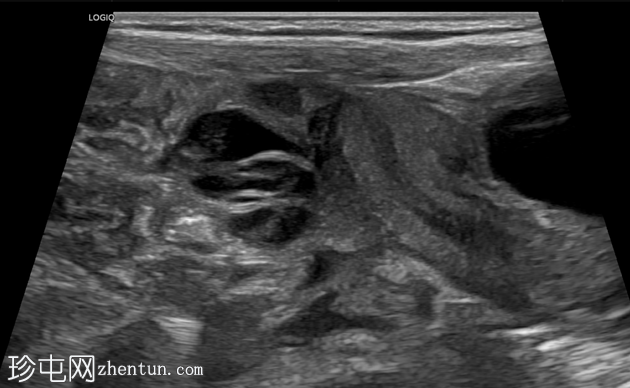

右侧努克氏疝管长约6毫米,内含部分子宫和卵巢(大小约1.5 x 1厘米)。在整个检查过程中,这些组织均保持原位。

上述超声特征清晰地显示了努克氏疝管的内容物及其延伸范围;其中包含患者的一侧卵巢和部分子宫组织。

这些特征符合卵巢努克氏疝的诊断。